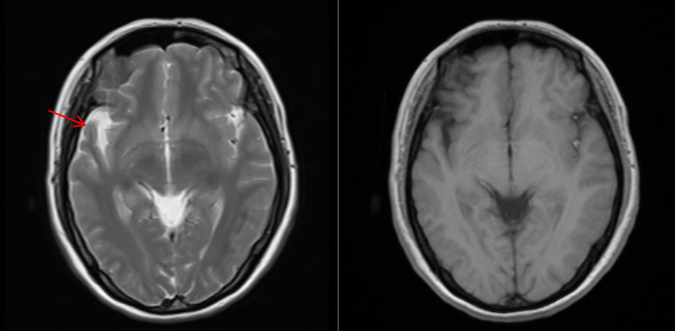

患者男,45岁,以头晕头痛为主诉就诊

图1右侧颞叶萎缩,外侧裂较对侧增宽(红色箭头)

图2双侧额顶叶大小、形态及信号未见明显异常